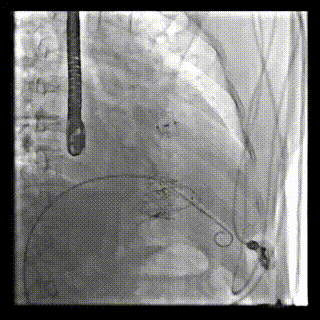

三例患者入院后,葛均波院士團隊周達新教授、潘文志教授、張源博士、陳莎莎博士及心超室的潘翠珍教授、李偉教授對患者的情況進行詳細評估和討論,最終決定為三例患者選擇LuX-Valve Plus40mm、50mm和50mm型號的瓣膜進行手術治療。手術后即刻拔除氣管插管,術后患者三尖瓣反流癥狀得到顯著改善,復查心超結果顯示人工三尖瓣瓣膜支架固定穩定,瓣葉關閉形態未見異常,未見明顯反流。